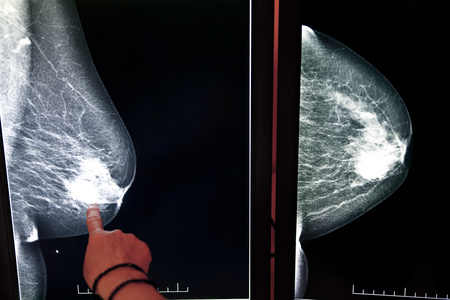

乳腺结节乳房的 x 射线照片

几张x光片,教你看乳房健康